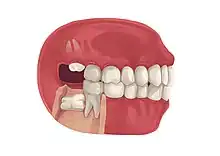

| Types | Full vs partially impacted, direction of impaction |

Impacted wisdom teeth is a condition where the third molars (wisdom teeth) are prevented from erupting into the mouth.[1] This can be caused by a physical barrier, such as other teeth, or when the tooth is angled away from a vertical position.[2] Completely unerupted wisdom teeth usually result in no symptoms, although they can sometimes develop cysts or neoplasms. Partially erupted wisdom teeth or wisdom teeth that are not erupted but are exposed to oral bacteria through deep periodontal pocket, can develop cavities or pericoronitis. Removal of impacted wisdom teeth is advised for the future prevention of or in the current presence of certain pathologies, such as caries (dental decay), periodontal disease or cysts. Prophylactic (preventative) extraction of wisdom teeth is preferred to be done at a younger age (middle to late teenage years) to take advantage of incomplete root development, which is associated with an easier surgical procedure and less probability of complications.[3]

Impacted wisdom teeth are often described by the direction of their impaction (forward tilting, or mesioangular being the most common), the depth of impaction and the age of the patient as well as other factors such as pre-existing infection or the presence of pathology (cysts, tumors or other disease).[5]: 143–144 Each of these factors is used to predict the difficulty (and rate of complications) when removing an impacted tooth, with age being the most reliable predictor[8] rather than the orientation of the impaction.[9]